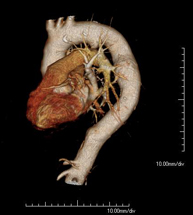

- Angio-TC Cardíaco

El angioTC Cardíaco o Coronariografía no invasiva es una prueba diagnóstica que consiste en el estudio de las arterias del corazón o arterias coronarias mediante el empleo de un equipo de TC Multidetector de última generación (64 coronas o filas de detectores) y de contraste yodado, obteniendo imágenes bi y tridimensionales. El TC Multidetector 64 o TCMD64 permite una adquisición de imágenes tan rápida, que se pueden valorar las arterias coronarias con una alta precisión anatómica (estrechamientos o estenosis, calcificaciones, variantes anatómicas, etc.), ya que, gracias a su rapidez, evita el artefacto que provoca el movimiento constante del corazón (tarda menos de diez segundos en adquirir unas 1000 imágenes). La información obtenida precisa de un tratamiento en estaciones de trabajo con programas especializados en la reconstrucción de las arterias coronarias que permiten valorar el número, la localización y las características de las lesiones. Toda esta información se obtiene de manera no invasiva: sólo se requiere la punción de una vena periférica (en el brazo). Es necesario que la frecuencia cardíaca no supere los 75 latidos por minuto, por lo que algunos pacientes deberán realizar un tratamiento previo con un fármaco betabloqueante.